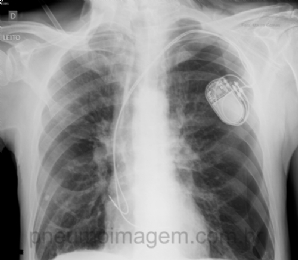

CASO CLÍNICO #11

Paciente do sexo masculino, 70 anos de idade, portador de DPOC classe C, apresentou quadro de hipersensibilidade do seio carotídeo e necessitou ser submetido à colocação de marca-passo cardíaco definitivo. Após o procedimento desenvolveu quadro de insuficiênci...